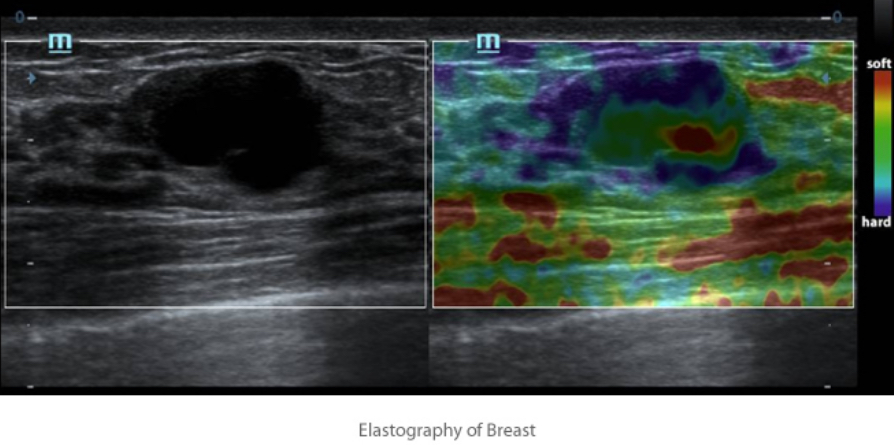

ElastografĂa Natural Touch

Basada en la Ășltima tecnologĂa patentada de Mindray, la elastografĂa Natural Touch reduce la dependencia en la tĂ©cnica de uso del usuario,

lo que mejora la reproducibilidad de la operaciĂłn para una mayor utilidad clĂnica.

- Mayor sensibilidad a la rigidez.

- Gran estabilidad y reproducibilidad.